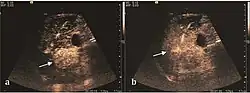

HCC appearance on 2D ultrasound is that of a solid tumor, with imprecise delineation, with heterogeneous structure, uni- or multilocular (encephaloid form). An "infiltrative" type is also described which is difficult to discriminate from liver nodular reconstruction in cirrhosis. Typically HCC invades liver vessels, primarily the portal veins but also the hepatic veins . Doppler examination detects a high speed arterial flow and low impedance index (correlated with described changes in tumor angiogenesis). The spatial distribution of the vessels is irregular, disordered. CEUS examination shows hyperenhancement of the lesion during the arterial phase. During the portal venous phase there is a specific "wash out" of ultrasound contrast agent (UCA) and the tumor appears hypoechoic during the late phase. Poorly differentiated tumors may have a stronger wash out leading to an isoechoic appearance to the liver parenchyma during portal venous phase. This appearance was found in approx. 30% of cases. The described changes have diagnostic value in liver nodules larger than 2 cm.

On CEUS examination, early HCC has an iso- or hypervascular appearance during the arterial phase followed by wash out during portal venous and late phase. There are studies showing that the wash out process is directly correlated with the size and features of neoplastic circulatory bed. Thus, highly differentiated HCC illustrates the phenomenon of late or even very late "wash out" while poorly differentiated HCC has an accelerated wash out at the end of arterial phase. It is therefore mandatory to analyze all these three phases of CEUS examination for a proper characterization of liver nodules. Tumor wash out at the end of the arterial phase allows the HCC diagnosis with a predictability of 89.5%. Some authors consider that early pronounced contrast enhancement of a nodule within 1–2 cm developed on a cirrhotic liver is sufficient for HCC diagnosis. These results prove that for a correct characterization of the lesions it is necessary to extend the examination time to 5 minutes or even longer.